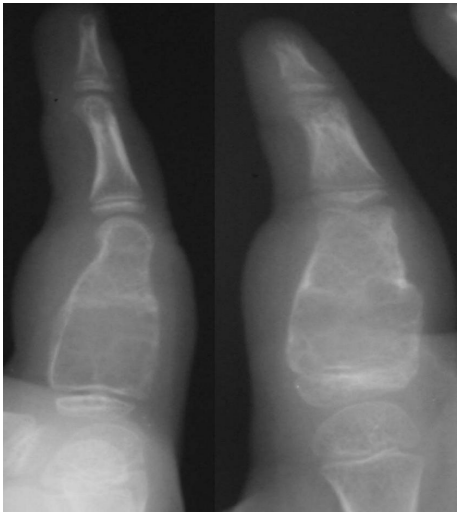

Case 2: A six-year-old girl presented with gradually increasing swelling in the left index finger over three months. She had sustained minor trauma one year earlier and radiograph at the time was normal. Clinically there was swelling involving the proximal phalanx of the left index finger. Swelling was hard and tender with normal overlying skin.

Radiograph showed expansile lytic lesion with thinned out cortex involving proximal phalanx of the index finger (figure 6). No abnormalities detected in the blood workup.

Patient underwent curettage of the lesion and packing with cancellous bone taken from the iliac crest (figure 7). The lesion healed in six months and there has been no recurrence.

Figure 6. Preoperative radiograph of case 2 showing the lesion in proximal phalanx of index finger.

Figure 7. Follow Up Radiograph of Case 2